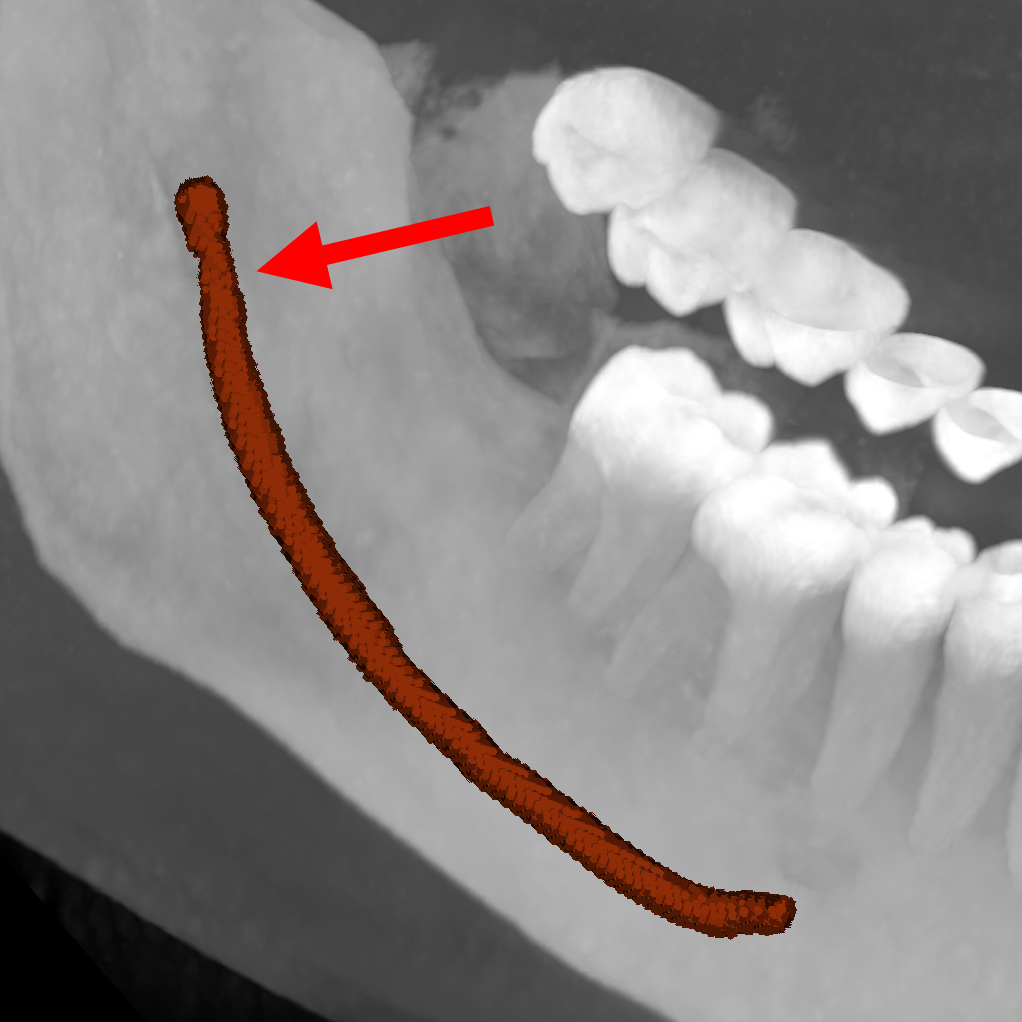

| ToothFairy[6, 5] | 3D | binary | 138 | Inferior Alveolar Canal |

We employ five public datasets featuring thin structures for validating the proposed Skeleton Recall Loss. The datasets span natural as well as medical images, covering a range of segmentation challenges, including both binary and multi-class segmentation problems in 2D as well as 3D contexts. An overview of the datasets can be found in Tab. 1. Among the three 2D datasets used in this study, the Digital Retinal Images for Vessel Extraction (DRIVE) dataset [32] was employed, focusing on retinal vessel segmentation. Additionally, structural inspection images designed for concrete crack segmentation (Cracks) [36] and aerial images of Massachusetts for road segmentation (Roads) [21] were included, highlighting the diversity of thin structures in natural and constructed environments. In the 3D domain, we incorporated two cutting-edge medical image segmentation challenge datasets. One of them was ToothFairy111https://toothfairy.grand-challenge.org/, which was a segmentation challenge on 3D Cone-Beam CTs [6, 5] featuring the inferior alveolar canal as the target structure. Additionally, the TopCoW222https://topcow23.grand-challenge.org/ dataset for topology-aware 3D segmentation of vessels in the Circle of Willis for CTA and MRA data [40] was utilized, encompassing binary as well as multi-class segmentation on 13 different subtypes of vessels. This diverse set of datasets enables a comprehensive evaluation of the proposed Skeleton Recall Loss, demonstrating generalizability of the method to a wide range of thin structure segmentation challenges in both 2D and 3D contexts.

5.1 Skeleton Recall Loss enables state-of-the-art segmentation of thin structures

The obtained results in Tab. 2 clearly show that our proposed Skeleton Recall Loss consistently surpasses previous thin structure segmentation losses on almost all datasets. For concrete crack segmentation[36], the results indicate better Dice and clDice performance at the cost of slightly worse Betti numbers than clDice Loss. However, Skeleton Recall Loss demonstrates the best clDice and Betti numbers for retinal vessel segmentation[32], yielding a Dice score just marginally behind clDice Loss. Notably, for the three datasets with an independent testset available, specifically Roads[21] and both of the 3D datasets, ToothFairy[6, 5] and TopCoW[40], we observe superior performance of our proposed Skeleton Recall Loss. This is further demonstrated by the qualitative results given in Fig. 5. Skeleton Recall Loss is also seen to be better than baselines, on both binary as well as multi-class settings of TopCoW as elaborated in following sections. We obtain this state-of-the-art performance while being architecture agnostic (Sec. 5.2) as well as overwhelmingly resource efficient (Sec. 5.3).